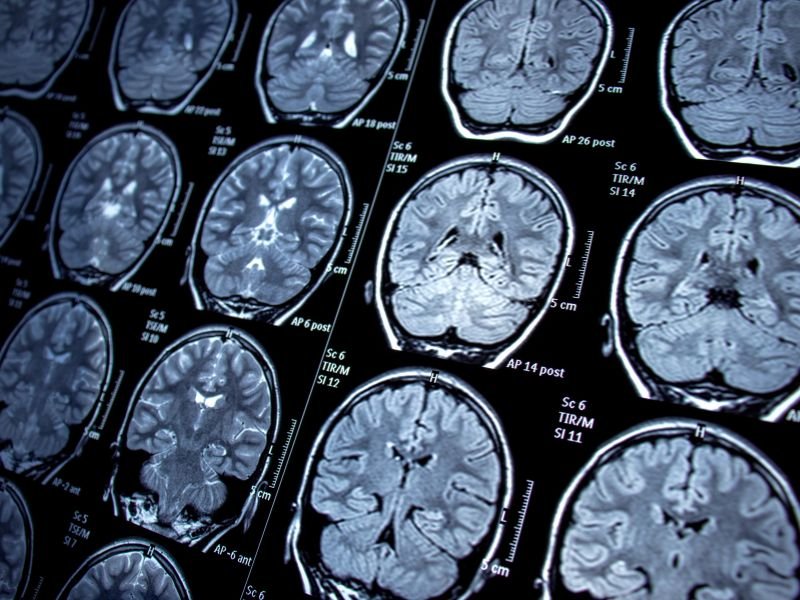

Tratamento Avançado para Enxaqueca em Tubarão A enxaqueca é uma condição neurológica que afeta milhões de pessoas em todo o mundo. Em Tubarão, o tratamento avançado para enxaqueca tem se tornado uma prioridade para muitos